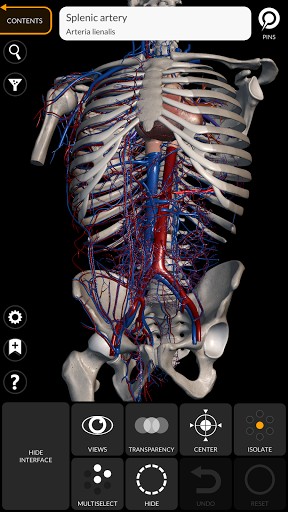

"Anatomy 3D Atlas" memungkinkan Anda mempelajari anatomi manusia dengan cara yang mudah dan interaktif.

Melalui antarmuka yang sederhana dan intuitif, Anda dapat mengamati setiap struktur anatomi dari sudut mana pun.

Model 3D anatomi sangat terperinci dan memiliki tekstur hingga resolusi 4k.

• Sistem kardiovaskular • Sistem

saraf • Sistem pernapasan • Sistem pencernaan • Sistem urogenital (pria dan wanita) • Sistem endokrin • Sistem limfatik • Sistem mata dan telinga FITUR • Antarmuka yang sederhana dan intuitif • Putar dan perbesar setiap model dalam ruang 3D • Opsi untuk menyembunyikan atau mengisolasi satu atau beberapa model yang dipilih • Filter untuk menyembunyikan atau menampilkan setiap sistem • Fungsi pencarian untuk menemukan setiap bagian anatomi dengan mudah • Fungsi penanda untuk menyimpan tampilan khusus • Rotasi cerdas yang menggerakkan pusat rotasi secara otomatis • Fungsi transparansi • Visualisasi otot melalui tingkat lapisan dari yang superfisial hingga yang terdalam • Dengan memilih model atau pin, istilah anatomi terkait akan muncul • Deskripsi otot: asal, • Tampilkan/ Sembunyikan antarmuka UI (sangat berguna dengan layar kecil) MULTIBAHASA • Istilah anatomi dan antarmuka pengguna tersedia dalam 11 bahasa: Latin, Inggris, Prancis, Jerman, Italia, Portugis, Turki, Rusia, Spanyol, Mandarin, Jepang, dan Korea • Istilah anatomi dapat ditampilkan dalam dua bahasa secara bersamaan PERSYARATAN SISTEM • Android 8.0 atau yang lebih baru, perangkat dengan RAM minimal 3GB Reversi